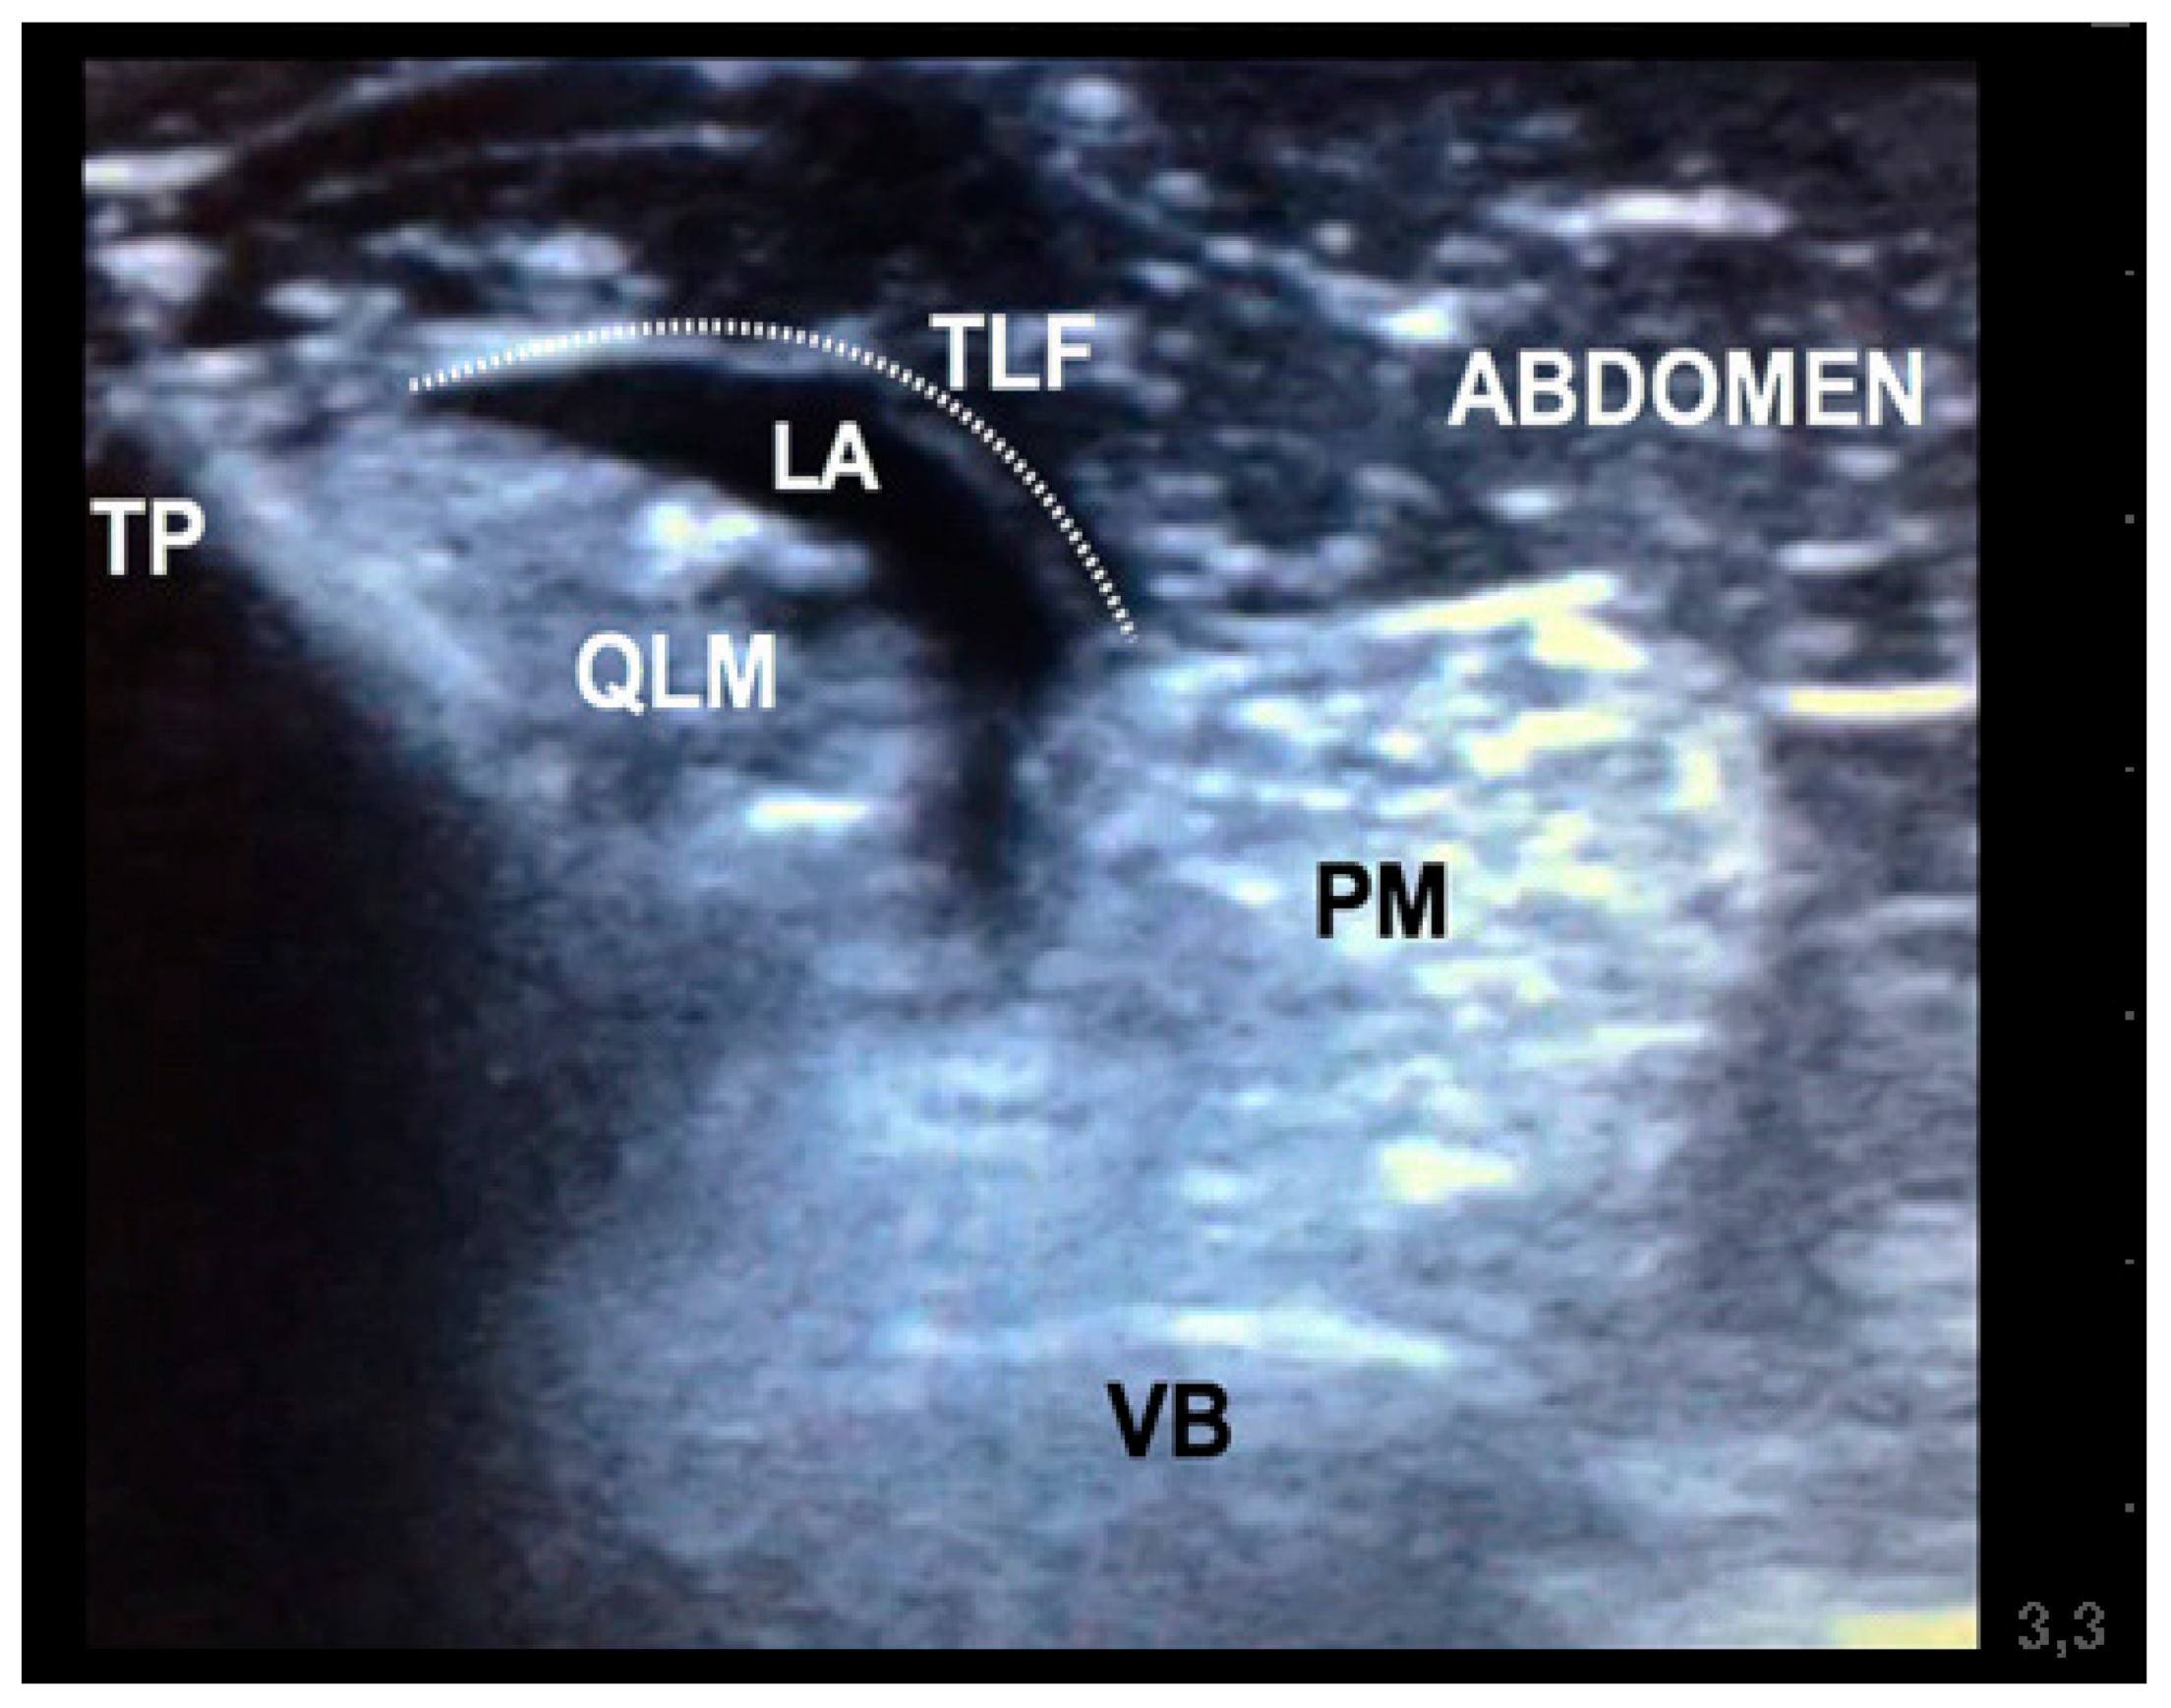

Figure 3. Ultrasound image obtained after injection in a canine carcass during quadratus lumborum block (QLB). The picture shows hydrodissection of the quadratus lumburom muscle from the psoas muscle and the thoracolumbar fascia, illustrating that the QLB block was successful. TP, transverse process of L2 vertebrae; VB, vertebral body of L2 vertebrae; QLM, quadratus lumborum muscle; PM, psoas muscle; LA, mixture of contrasts; TLF, thoracolumbar fascia.

The US-guided QLB technique was performed in the following manner. The US probe was placed in a transverse plane over the lumbar muscles just caudal to the last rib using a paramedian sagittal oblique (subcostal) approach described by Elsharkawy [13] in humans. Once in position, the probe was rotated slightly cranial to visualise the following anatomical structures: quadratus lumborum muscle, psoas muscle, lateral aspect of the body of the first lumbar vertebrae, and the transverse process of the first lumbar vertebrae (Figure 1). The needle was inserted in-plane and advanced at a 45º angle from dorsolateral to ventromedial until its tip was placed between the quadratus lumborum and psoas muscles (Figure 2). At this location, the mixture was injected into the fascial plane. A volume of less than 1 mL of saline was first injected to confirm the correct position of the tip of the needle. The injection was considered as correct when hydrodissection of the quadratus and psoas muscles together with the ventral movement of the thoracolumbar fascia was noted (Figure 3). If this pattern was not visualised, the needle was redirected until this hydrodissection was observed.